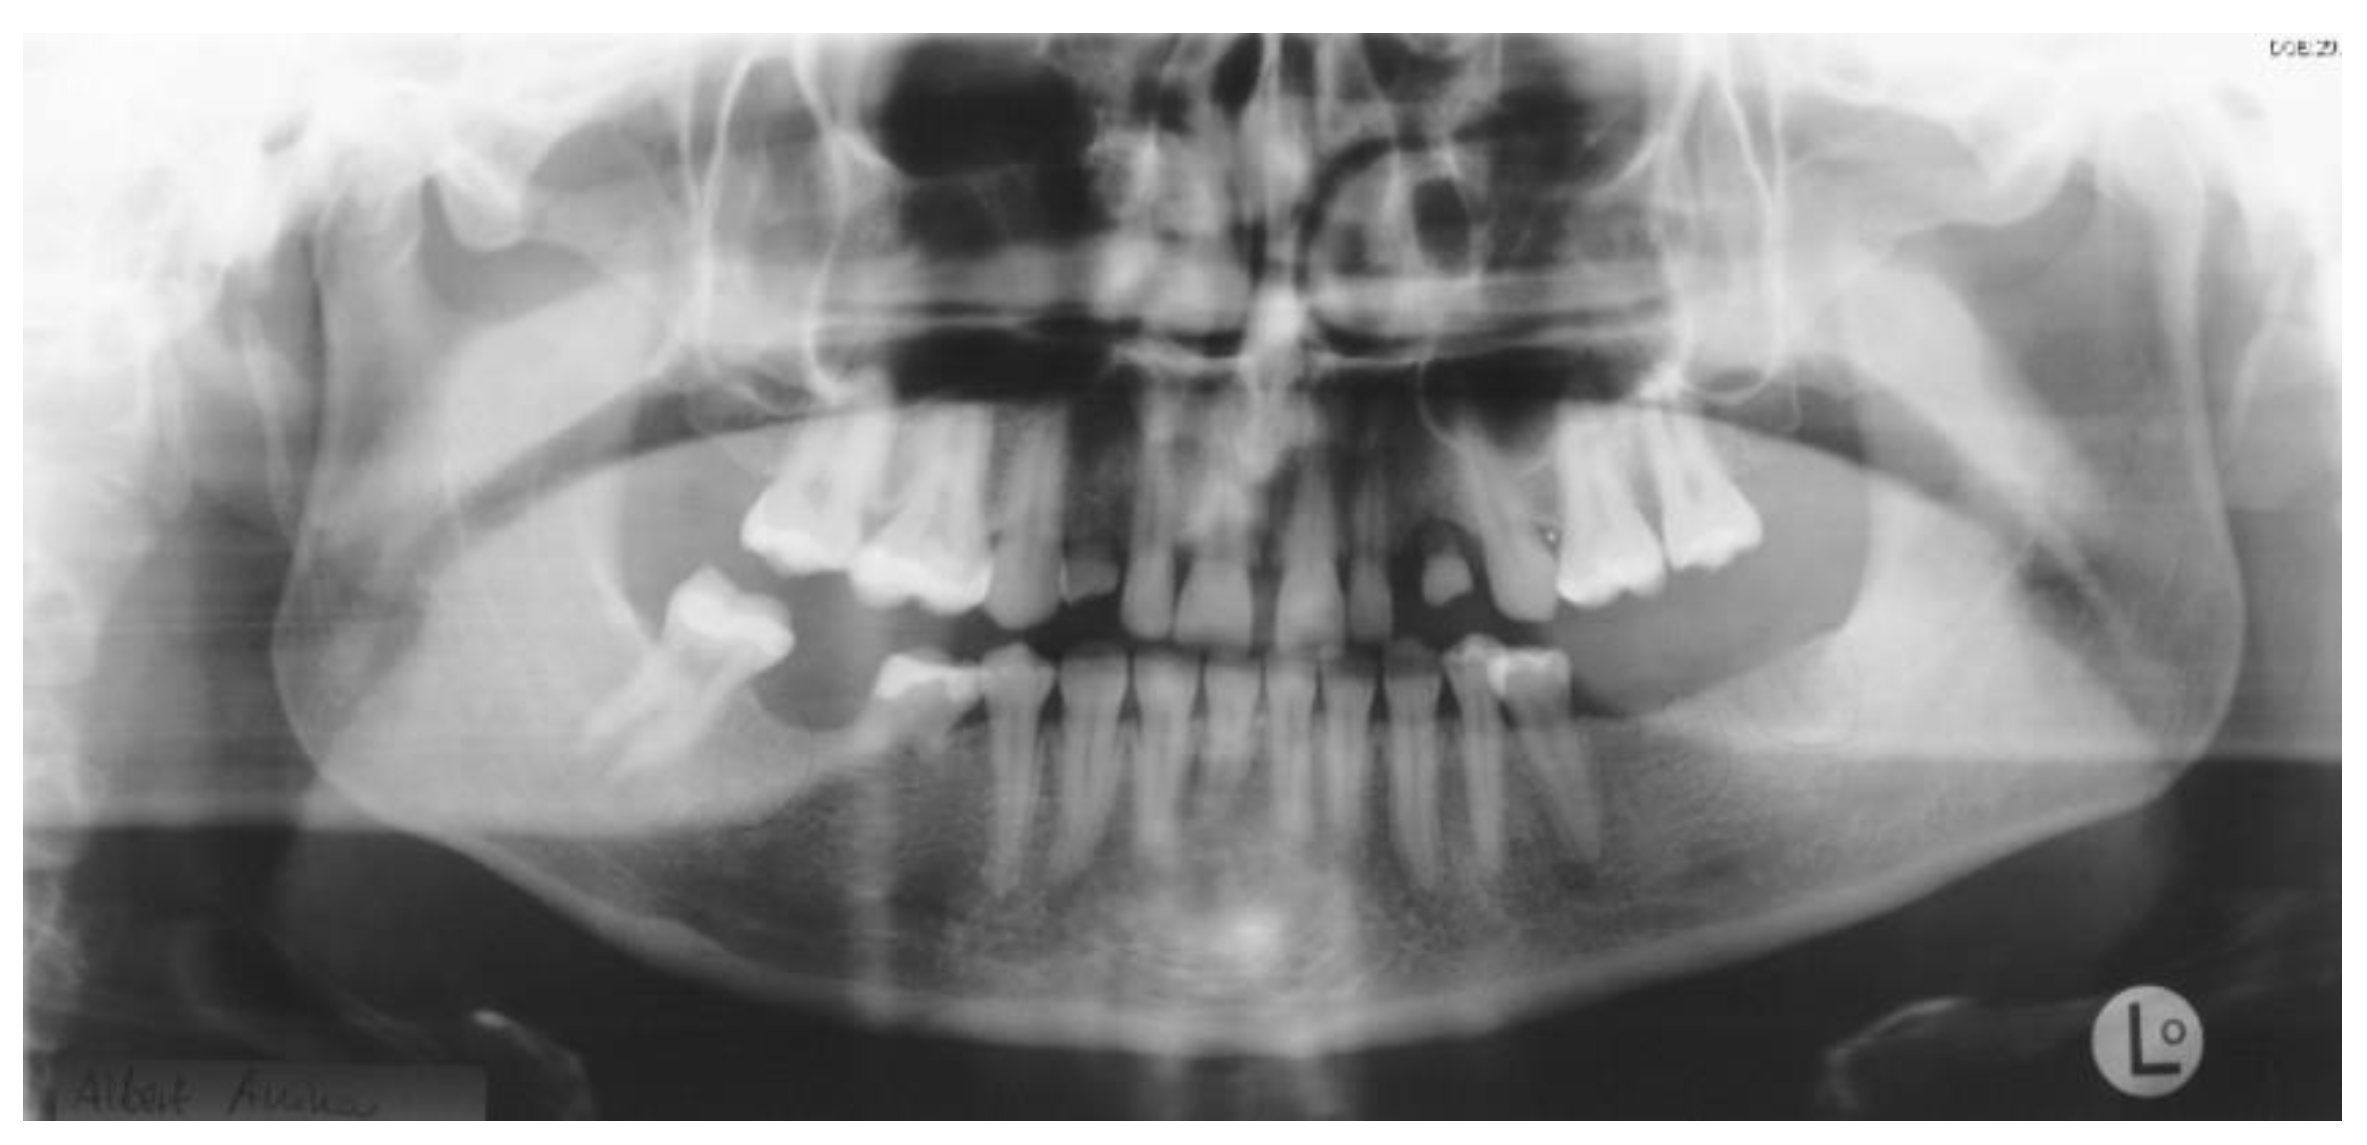

Figure 2.

Panoramic radiography after bone graft, nerve lateralization, and placement of dental implants in edentulous sites with adequate bone volume.

As soon as the orthodontic treatment was completed, the patient returned for dental implant planning. Regardless of adequate teeth alignment, the wide interproximal spaces, disproportional teeth dimensions, and abnormal occlusion increased the complexity of the case (Figure 1). Radiological examinations showed a reduced bone height at the edentulous site. In consideration of a bone atrophy in the upper and lower jaws, a two-stage surgical procedure was planned, which included bilateral sinus lift, nerve lateralization and placement of dental implants at the sites 16, 15, 12, 22, 35, 36, 32, 42, and 45 (Figure 2).